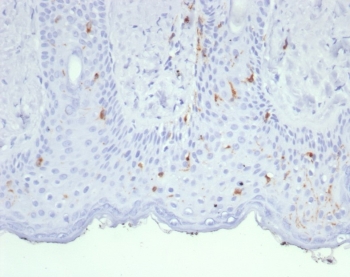

IHC staining of FFPE human skin tissue with Langerin antibody (clone LGRN/7430). HIER: boil tissue sections in pH 9 10mM Tris with 1mM EDTA for 20 min and allow to cool before testing.